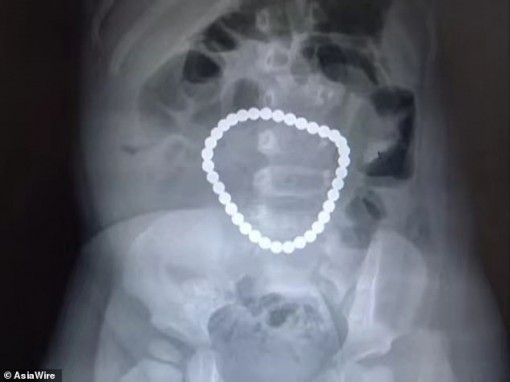

• Cả nhà phát hoảng khi thấy chuỗi hạt nằm trong bụng con gái 1 tuổi

Cả nhà phát hoảng khi thấy chuỗi hạt nằm trong bụng con gái 1 tuổi

04-08-2019 17:27

Gia đình của bé gái phát hoảng khi kết quả chụp X-quang ở một phòng khám địa phương cho thấy một chuỗi hạt khá to trong bụng em.